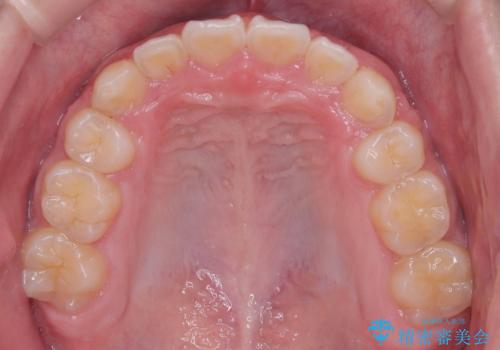

八重歯・歯並びのデコボコとディープバイトを改善した抜歯ワイヤー矯正症例

八重歯などの歯列のデコボコが綺麗に改善され、患者様にも大変喜んでいただけました。また、咬み合わせが深い「ディープバイト」も併せて改善し、見た目だけでなく機能面でもバランスの取れた咬合を獲得しています。